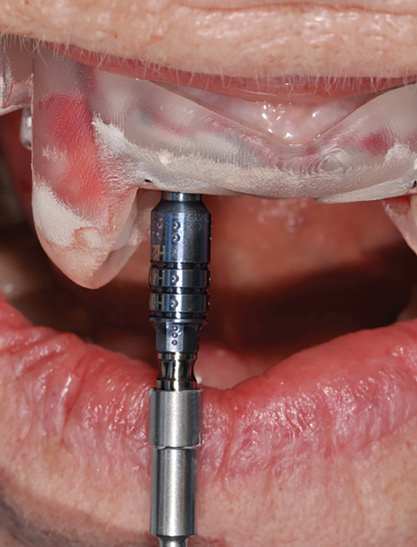

Fig 14. The printed static guide is used to precisely control preparation of osteotomy (Fig 14) and delivery of the implant through the guide (Fig 15).

Figure 14

Fig 15. The printed static guide is used to precisely control preparation of osteotomy (Fig 14) and delivery of the implant through the guide (Fig 15).

Figure 15